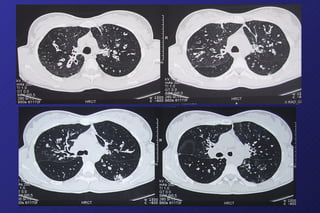

BRONCHIECTASIE MANIFESTAZIONI CLINICHE Nelle fasi iniziali episodi ricorrenti di tosse, espettorazione muco-purulenta,  emoftoe (modesta) spesso dolore toracico (per flogosi peribronchiectasica) Nelle fasi più avanzate tosse ed espettorazione abituale, dispnea da sforzo, limitazioni  nella vita quotidiana scadimento delle condizioni generali (magrezza) Reperti obiettivi toracici rumori aggiunti discontinui (a bassa tonalità) (“coarse crackles”) rumori continui in- espiratori, di medio-alta tonalità (“ronchi”) Segni radiologici al Rx-torace (trama accentuata, immagini bronchiali, addensamenti) alla TAC torace (HRCT): dilatazioni cilindriche, cistiche, varicose

FIBROSI CISTICA DIAGNOSI Rx-torace e TAC torace bronchiectasie cistiche, specie nei campi superiori Test di primo screening Test del sudore (poco sensibile) Test di conferma test genetici (mutazioni più frequenti) Test funzionali respiratori variabili con la gravità e/o durata della malattia in genere in senso ostruttivo

BRONCHIECTASIE MANIFESTAZIONI CLINICHENelle fasi iniziali episodi ricorrenti di tosse, espettorazione muco-purulenta, emoftoe (modesta) spesso dolore toracico (per flogosi peribronchiectasica) Nelle fasi più avanzate tosse ed espettorazione abituale, dispnea da sforzo, limitazioni nella vita quotidiana scadimento delle condizioni generali (magrezza) Reperti obiettivi toracici rumori aggiunti discontinui (a bassa tonalità) (“coarse crackles”) rumori continui in- espiratori, di medio-alta tonalità (“ronchi”) Segni radiologici al Rx-torace (trama accentuata, immagini bronchiali, addensamenti) alla TAC torace (HRCT): dilatazioni cilindriche, cistiche, varicose

FIBROSI CISTICA DIAGNOSIRx-torace e TAC torace bronchiectasie cistiche, specie nei campi superiori Test di primo screening Test del sudore (poco sensibile) Test di conferma test genetici (mutazioni più frequenti) Test funzionali respiratori variabili con la gravità e/o durata della malattia in genere in senso ostruttivo